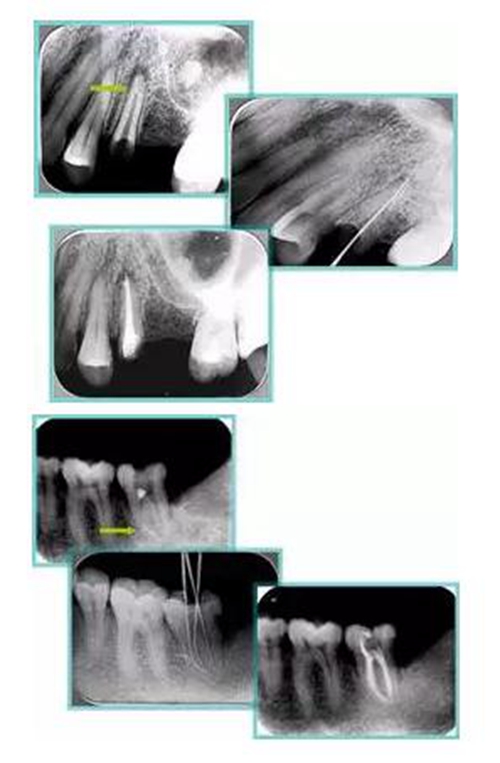

2. X 線片

共有 4 張 X 線片,分別是術(shù)前、診斷絲 、主牙膠尖確認(rèn)、術(shù)后。

( 1 )術(shù)前:術(shù)前 X 線片用來(lái)了解牙齒的大概情況。術(shù)前預(yù)期為多根牙時(shí) X 線片應(yīng)偏頭拍攝。

( 2 )診斷絲:根據(jù)術(shù)前 X 線片進(jìn)行開(kāi)髓、根管的初步預(yù)備后,需要插入診斷絲,用來(lái)指示工作器械位置。常用 10 號(hào)或 15 號(hào)擴(kuò)大器作為診斷絲插入牙髓腔。

( 3 )主牙膠尖確認(rèn):通過(guò)術(shù)前預(yù)期和診斷絲診斷,明確工作長(zhǎng)度、牙根走向,進(jìn)行根管預(yù)備。之后應(yīng)進(jìn)行主牙膠尖(中銼)確認(rèn),已明確根管是否適合充填。

( 4 )術(shù)后:觀察治療效果。